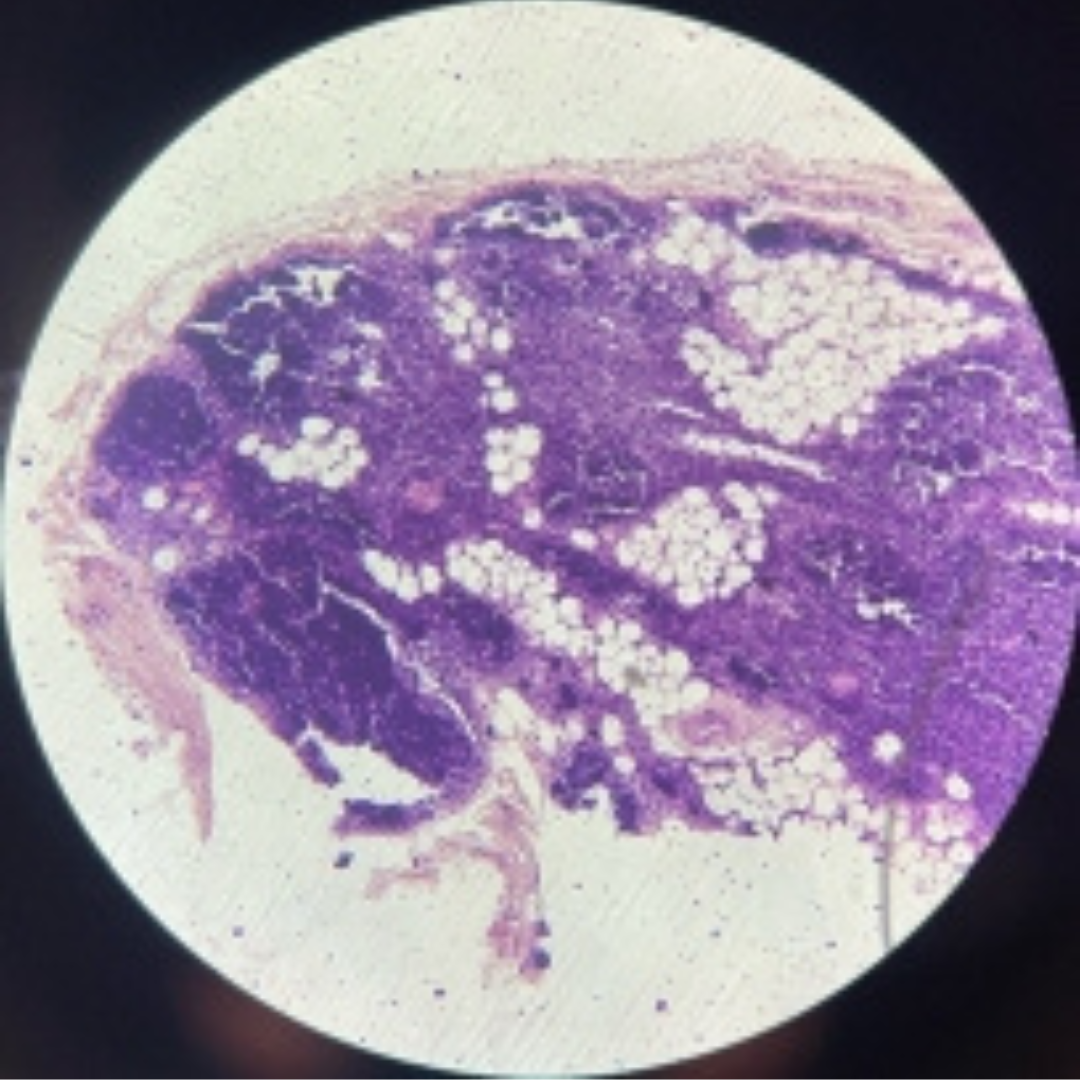

Thymus (Involuted)

30

New cards

Thymus (Involuted)

31

New cards

Thymus (Involuted)

35

New cards

Thymus (Involuted)